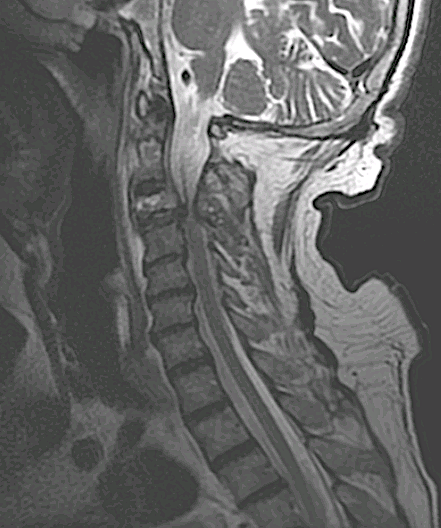

Paciente de 71 años que presenta enfermedad oncológica en estadio paliativo por tumor renal de años de evolución. Presentó fractura patológica C3 con clínica de tetraparesia súbita e incapacidad para mantener bipedestación (ASIA C). En comité de Neuroncología se acordó tratamiento quirúrgico paliativo.

Se realizó una descompresión posterior del arco de C3 asociando una artrodesis occipitocervical. La afectación del pedículo/pars de C2 por el tumor recomendaba obviar esa vértebra en la reconstrucción.

Obsérvese afectación pedículo/pars C2 por el tumor